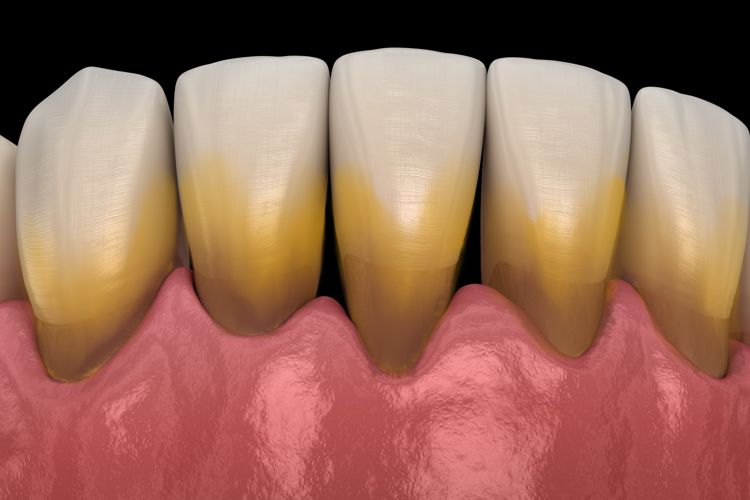

پلاک های دندانی چیست؟

- پلاک های دندانی چه گونه ایجاد میشوند؟

پلاکها و باکتریهای سطح دندان و لثه آن میتوانند گازهای بدبو ترشح کنند و منجر به بوی بد دهان شوند. از سوی دیگر پلاک ها می توانند باعث ایجاد لکه های سطحی به رنگ زرد یا خاکستری روی دندان ها شود و باعث زرد به نظر رسیدن دندان ها و یا تغییر رنگ آنها میباشد. در درمان جرم گیری لکههای قهوهای یا زرد رنگی را که روی دندان شما ایجاد شده است یا حتی برخی از مواد چسبناک سفید را از بین میبرد. برخی از لکه های دندانی و جرم های ایجاد شده در بالای لثه و سطح دندان ها معمولا سفید مایل به کرم تا زرد رنگ و گاهی هم خاکستری است که باعث تجمع پلاک باکتریال می شود. در درمان جرم گیری گاها لکه های سیاه رنگ ایجاد شده که ناشی از عفونت دندان نباشد نیز بر طرف میگردد.